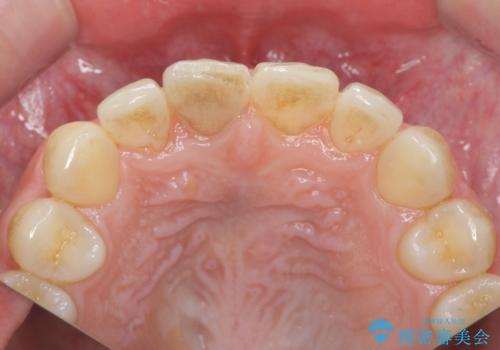

前歯の変色 打撲により失活した前歯の根管・セラミック治療

- 変色してきた前歯の形態回復、色調の改善を求めて来院されました。

X線検査、歯髄(歯の神経)の検査を行ったところ、失活(歯の神経の死んだ状態)であると診断されました。

放置すると変色が進行するだけでなく、根尖病変も形成される恐れが強いことから、根管治療を行ったのちセラミッククラウンによる審美性の改善を計画します。

自然な色調をセラミッククラウンで再現することができ、審美性の改善に大変喜んでいただくことができました。